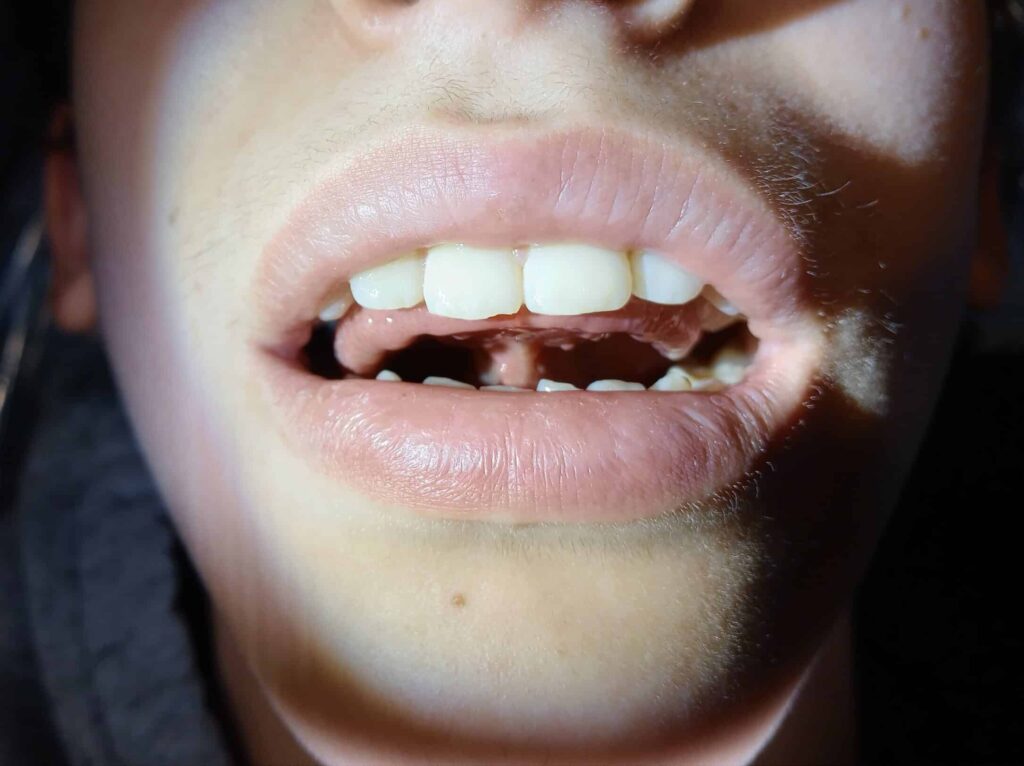

Pre tongue surgery

Pre tongue tie surgery